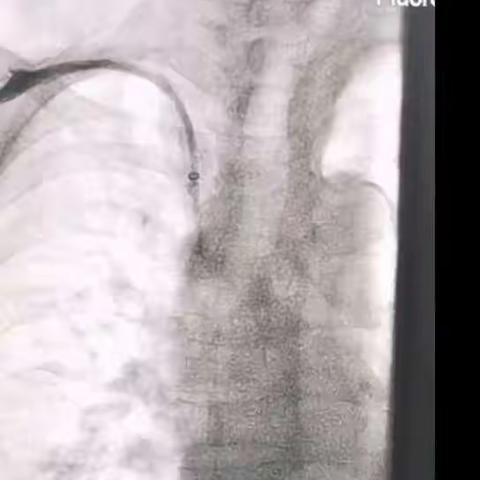

导管在手,成功在我